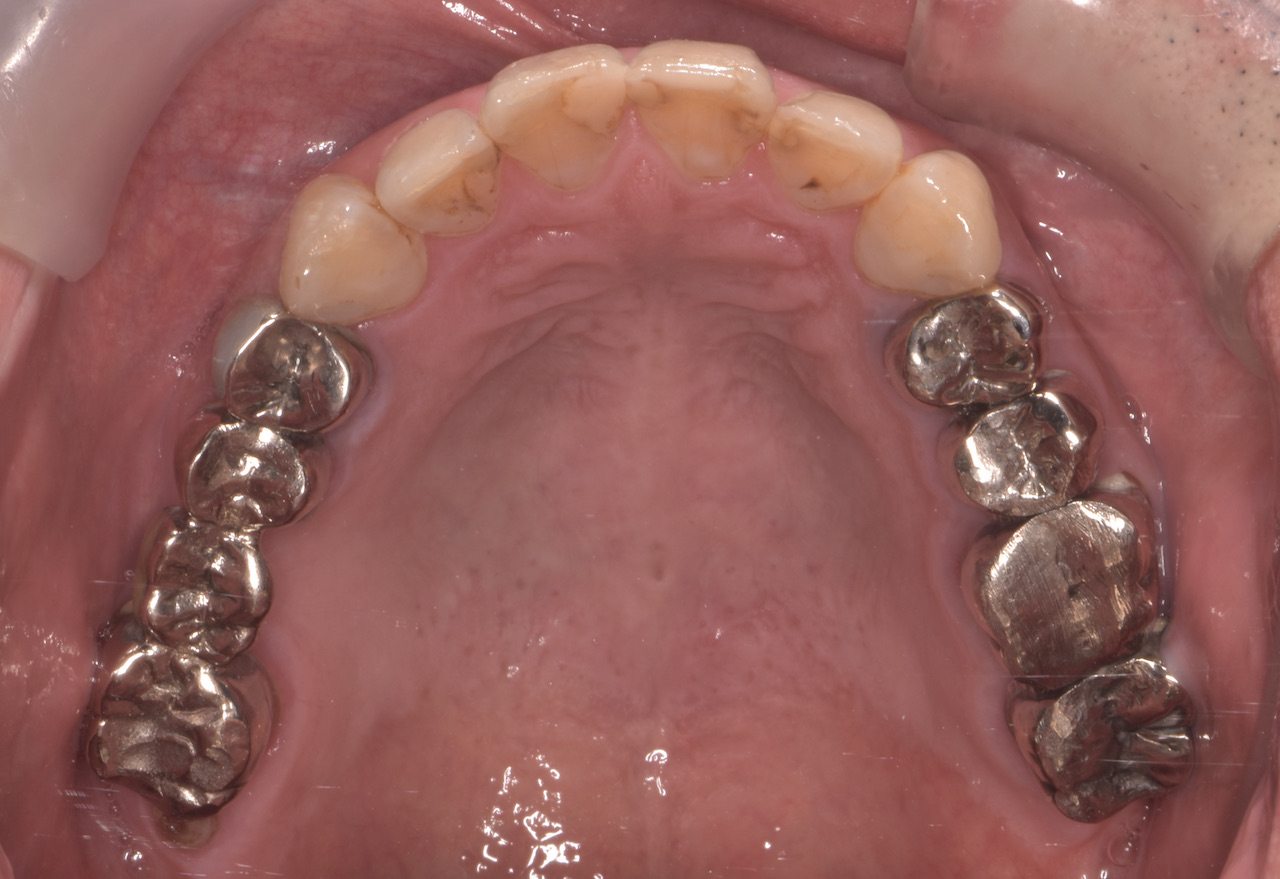

この患者さんは50代の男性で、若い時から様々な歯科治療をなさり、それに伴って抜歯をされたり、咬めなくなったそうです。そのなかで徐々に咬む位置がが分からなくなってきたとい言うお悩みで名取歯科医院にご来院されました。 全顎的に複数の治療部位で、インプラント・ブリッジ・ダイレクトボンディング・セラミッククラウンなど、適切な治療方法を組み合わせて包括的な治療を終え顎関節症の改善と咬めないという永きにわたるお悩みを解消しました。

顎関節の精密検査を行うと顎の状態も左右で異なり、咬み合わせもズレが大きくなったことで歯が欠けるなど、不調の理由がわかりました。

顎関節の軟骨(関節円板)がずれ、それに伴って咬み合わせが変化しても当時の歯科医師が適切な咬み合わせ(咬合調整)しなかったため、そのストレスが長年にわたり顎関節に影響し、痛みを生じてきたと検査から考えられました。

精密検査の中で「T-scan」という咬み合わせの専用の機械を使って診断すると、奥歯以外ではしっかり咬む箇所がなく、明らかに咬み合わせのバランスが良くありません。

全顎的に複数の治療部位で、インプラント・ブリッジ・ダイレクトボンディング・セラミッククラウンなど、適切な治療方法を組み合わせて包括的な治療を進めました。

治療前